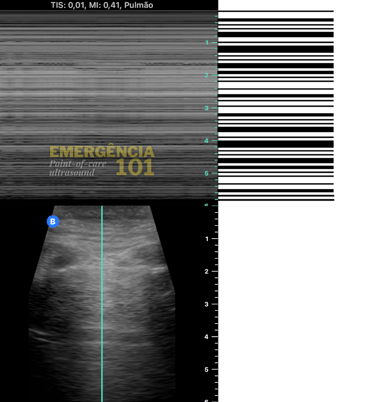

Em algumas situações, pode ser difícil visualizar se há ou não deslizamento pleural pelo modo B do ultrassom, como na avaliação dos ápices pulmonares, que são regiões naturalmente menos ventiladas, e/ou em pacientes com movimentos respiratórios menos intensos (imagine um paciente intubado com sedação profunda e volume corrente pequeno), nesses casos é possível utilizar o modo M (motion) do ultrassom para registrar o movimento da pleura, gerando dois sinais característicos:

Sinal do código de barras: ausência de deslizamento pleural. (figura 7c)

Figura 7c. Barcode sign (Sinal do código de barras no modo M), significando ausência de deslizamento pleural no campo pulmonar avaliado, não necessariamente causado por pneumotórax. Acervo pessoal do autor.